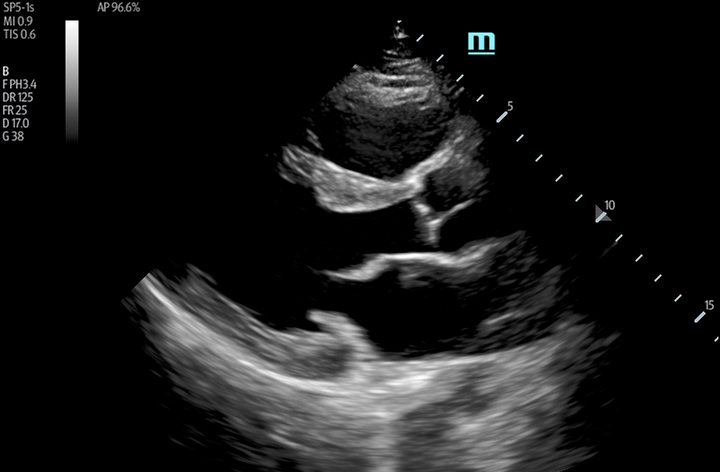

The TE7 Ultrasound System Crystal Series 2.0 is the system of choice from routine point-of-care exams to extreme situations when every second counts. With best-in-class image quality, a sleek form factor, and breakthrough needle visualization advancements, the TE7 System is designed to provide superior performance for rapid, confident exams and procedures in the fast paced, point of care environment.

The TE7 System incorporates an intuitive touchscreen and focused point-of-care protocols designed to standardize and reduce exam times. The System’s second generation iVocal voice recognition technology and new programmable-button transducer technology allows for a hands-free scanning experience, ideal for sterile environments.